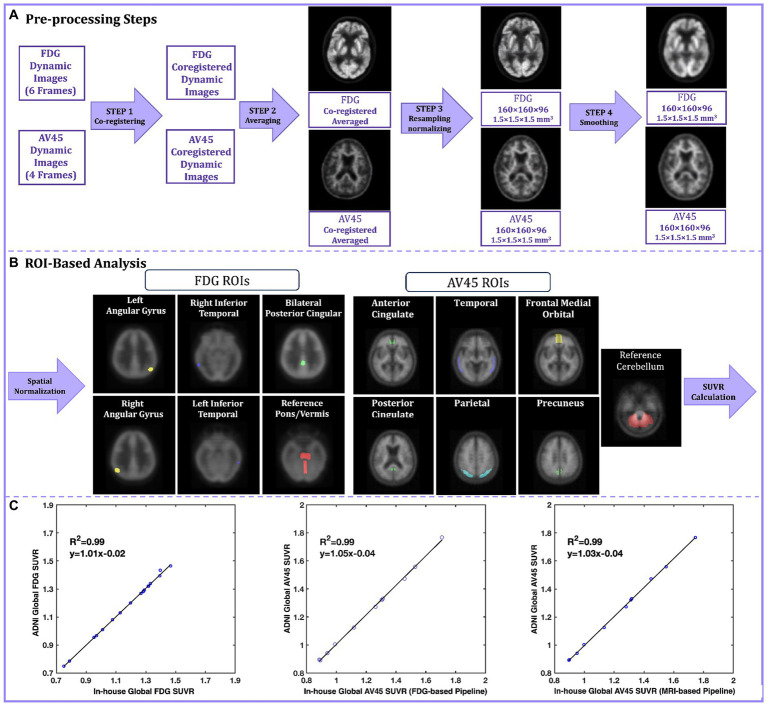

最近,脑结构磁共振成像(MRI)和功能磁共振成像(MRI)研究界将大量精力集中在解决可重复性危机上,而本文认为脑正电子发射断层扫描(PET)研究的基础更加脆弱,落后于解决 MRI 可重复性问题的努力。我们首先考察了当前有助于神经成像数据分析可重复性的各种因素,包括科学标准、分析计划预注册、数据和代码共享、容器化工作流程和标准化处理管道。然后,我们将重点关注这些因素在脑 MRI 和脑 PET 之间的现状差异。为了证明进一步开发这些可重复性因素将对脑 PET 研究产生的积极影响,我们介绍了一个案例研究,该案例说明了一家实验室在试图复制社区标准脑 PET 处理管道时所面临的诸多挑战。我们确定了脑 PET 社区可以提高可重复性的关键领域,包括 PET 专用期刊之间更严格的报告政策、数据存储库、容器化分析工具和标准化处理管道。此外,还讨论了其他解决方案,如强制预注册、数据共享、将代码可用性作为资助条件、在线论坛和标准化报告模板等。在脑 PET 研究界加强这些可重复性因素有可能释放脑 PET 研究的全部潜力,推动其走向更有影响力的未来。

While a great deal of recent effort has focused on addressing a perceived reproducibility crisis within brain structural magnetic resonance imaging (MRI) and functional MRI research communities, this article argues that brain positron emission tomography (PET) research stands on even more fragile ground, lagging behind efforts to address MRI reproducibility. We begin by examining the current landscape of factors that contribute to reproducible neuroimaging data analysis, including scientific standards, analytic plan pre-registration, data and code sharing, containerized workflows, and standardized processing pipelines. We then focus on disparities in the current status of these factors between brain MRI and brain PET. To demonstrate the positive impact that further developing such reproducibility factors would have on brain PET research, we present a case study that illustrates the many challenges faced by one laboratory that attempted to reproduce a community-standard brain PET processing pipeline. We identified key areas in which the brain PET community could enhance reproducibility, including stricter reporting policies among PET dedicated journals, data repositories, containerized analysis tools, and standardized processing pipelines. Other solutions such as mandatory pre-registration, data sharing, code availability as a condition of grant funding, and online forums and standardized reporting templates, are also discussed. Bolstering these reproducibility factors within the brain PET research community has the potential to unlock the full potential of brain PET research, propelling it toward a higher-impact future.